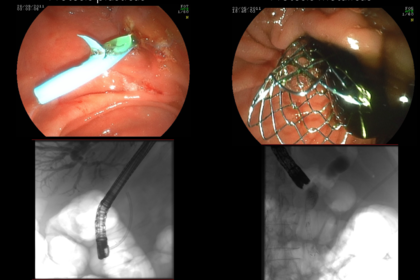

El objetivo es canular la papila y uno o los dos conductos (colédoco, Wirsung). Esta maniobra consiste en introducir en la papila un pequeño tubo plástico (catéter o cánula). Para llegar hasta la zona de la papila se utiliza un endoscopio o sonda óptica flexible que se introduce por la boca. Habitualmente, se emplea un endoscopio especial para la CPRE llamado duodenoscopio. La canulación de la papila y del conducto deseado (colédoco y/o Wirsung) es uno de los puntos más cruciales en la CPRE. En ocasiones, esta maniobra es muy compleja y, de hecho, la CPRE se considera como una de las intervenciones más difíciles de la Endoscopia Digestiva. Una vez canulada la papila se inyecta a través del catéter un contraste radiológico. De esta forma se “dibujan” los conductos que pueden observarse con radiografías fijas o bien de forma dinámica (fluoroscopia). Por lo tanto, la CPRE se realiza habitualmente en una sala provista de rayos X. Para que el paciente esté tranquilo durante la CPRE, pueden utilizarse distintos tipos de sedación: anestesia general, sedación profunda o sedación consciente.

Una de las maniobras terapéuticas más frecuentes es seccionar (cortar) el músculo esfinteriano de la papila para agrandar su abertura al duodeno. Es lo que se denomina esfinterotomía o papilotomía, que puede hacerse en la vertiente del colédoco (esfinterotomía biliar), en la del páncreas (esfinterotomía pancreática), o en las dos. La esfinterotomía se realiza pasando una corriente eléctrica a través de un catéter especial denominado esfinterotomo para cortar la papila. El orificio papilar puede también agrandarse dilatándolo con un balón. Es lo que se denomina esfinteroplastia.

Algunas otras de las múltiples intervenciones que pueden llevarse a cabo en la CPRE son: extracción de piedras en el colédoco (coledocolitiasis), colocación de tubos plásticos o metálicos (prótesis o stents) en el colédoco o páncreas para tratar estrecheces (estenosis), fístulas u otros problemas que afecten a los conductos. Estas prótesis pueden ser temporales o permanentes, según el tipo de obstrucción.